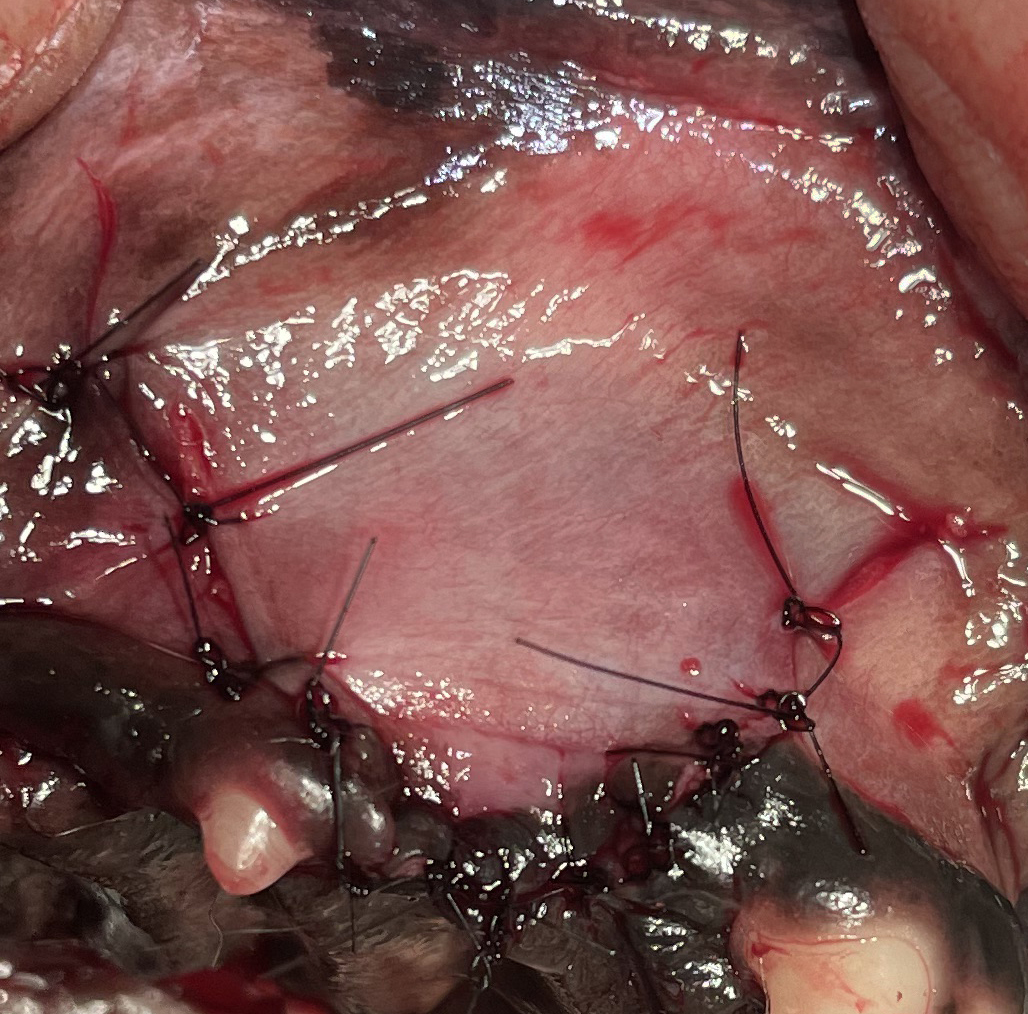

簡単に手術方法をご説明しますと、その部位の抜歯、殺菌を行い、滅菌下にて製剤を注入し、その後に縫合いたします。

症例:下顎のP4 - M1 - M2の重度歯周病による下顎骨折のリスク

*下の画像をご覧ください。青の矢印(②)で描写された幅が本来の下顎の幅です。つまり歯周病がなければ歯(M1)と下顎骨が一緒になって下顎の幅と考えられるわけです。しかし歯周病によって赤の矢印の幅分まで下顎が薄くなっております。特に①などに関しては骨折のリスクがあると考えてよいでしょう。

続いて下顎のM1の下方から皮質骨を採材しボーンミルで粉砕しリグロスと混合し滅菌カップにいれて保存します。犬歯内側を切開し犬歯内側にいれて縫合します。